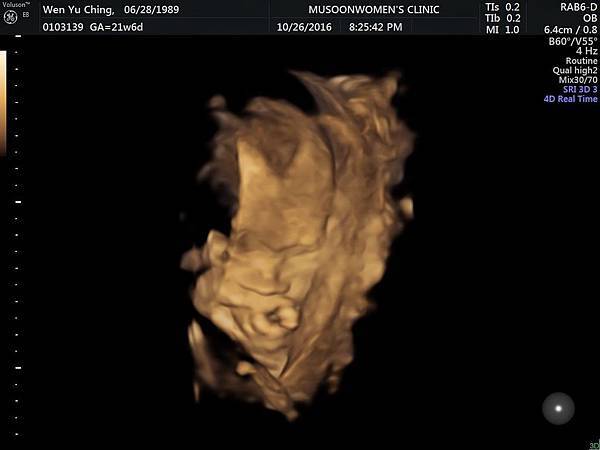

10.26_21w6d (3)

懷孕 (21-24W)高層次超音波: 左心室有一 顆小白點 嘖嘖